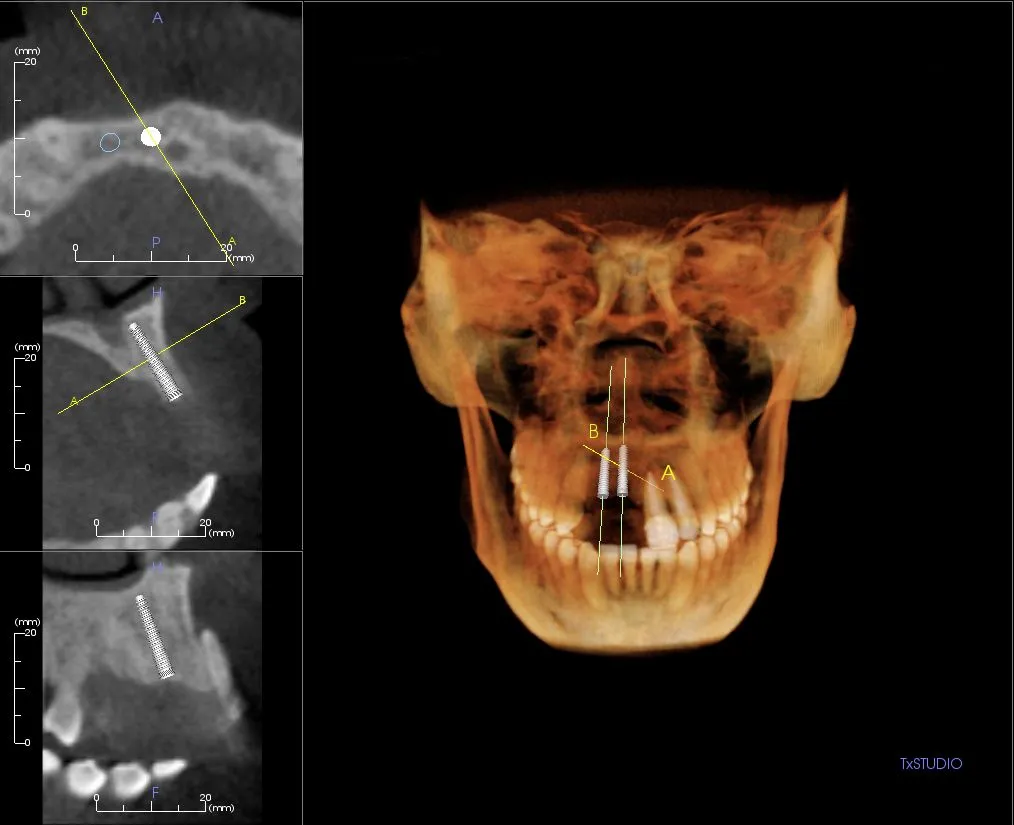

The current emerging standard of care in dentistry and dental implantology is the use of three dimensional x-ray studies. The 3-D images allow the doctor to collect the needed and highly valuable diagnostic information so they can best plan and deliver dental and surgical care.

i-CAT Cone Beam 3D Imaging provides three-dimensional imaging to the dental community, right in the practice office. The system offers active sagittal, coronal, and axial viewing and manipulation. It enhances diagnosis and treatment planning by providing more accurate imaging. Using the 3-D mapping tool, dental professionals can easily format and select desired slices for immediate viewing. Cone Beam imaging delivers quicker and easier image acquisition a typical scan takes only 20 seconds.

The diagnostic images from the i-CAT scanner can be easily converted into a third party software (i.e. Simplant, Nobel guide, Dolphin, etc.) for pre-surgical evaluation and computer guided surgery. The doctor will receive a viewable animation to help him measure and analyze your case from every aspect. The data can also be used to fabricate your surgical guides.